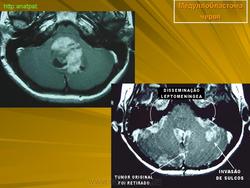

Медуллобластома - это опухоль, которая возникает из примитивных и эмбриональных клеток ЦНС. Локализируется исключительно в мозжечке и представляет 15-20% от детских опухолей мозга. 20% медуллобластом появляется в зрелом возрасте.

Это быстро растущая опухоль, очень злокачественна, имеющая тенденцию распространяться вдоль путей движения ликвора.

Вследствие локализации в мозжечке, обструкция путей циркуляции ликвора является достаточно частой и ранней, с последующей гидроцефалией. Синдром повышенного внутричерепного давления наряду с расстройствами равновесия, являются наиболее частыми и ранними признаками и симптомами.